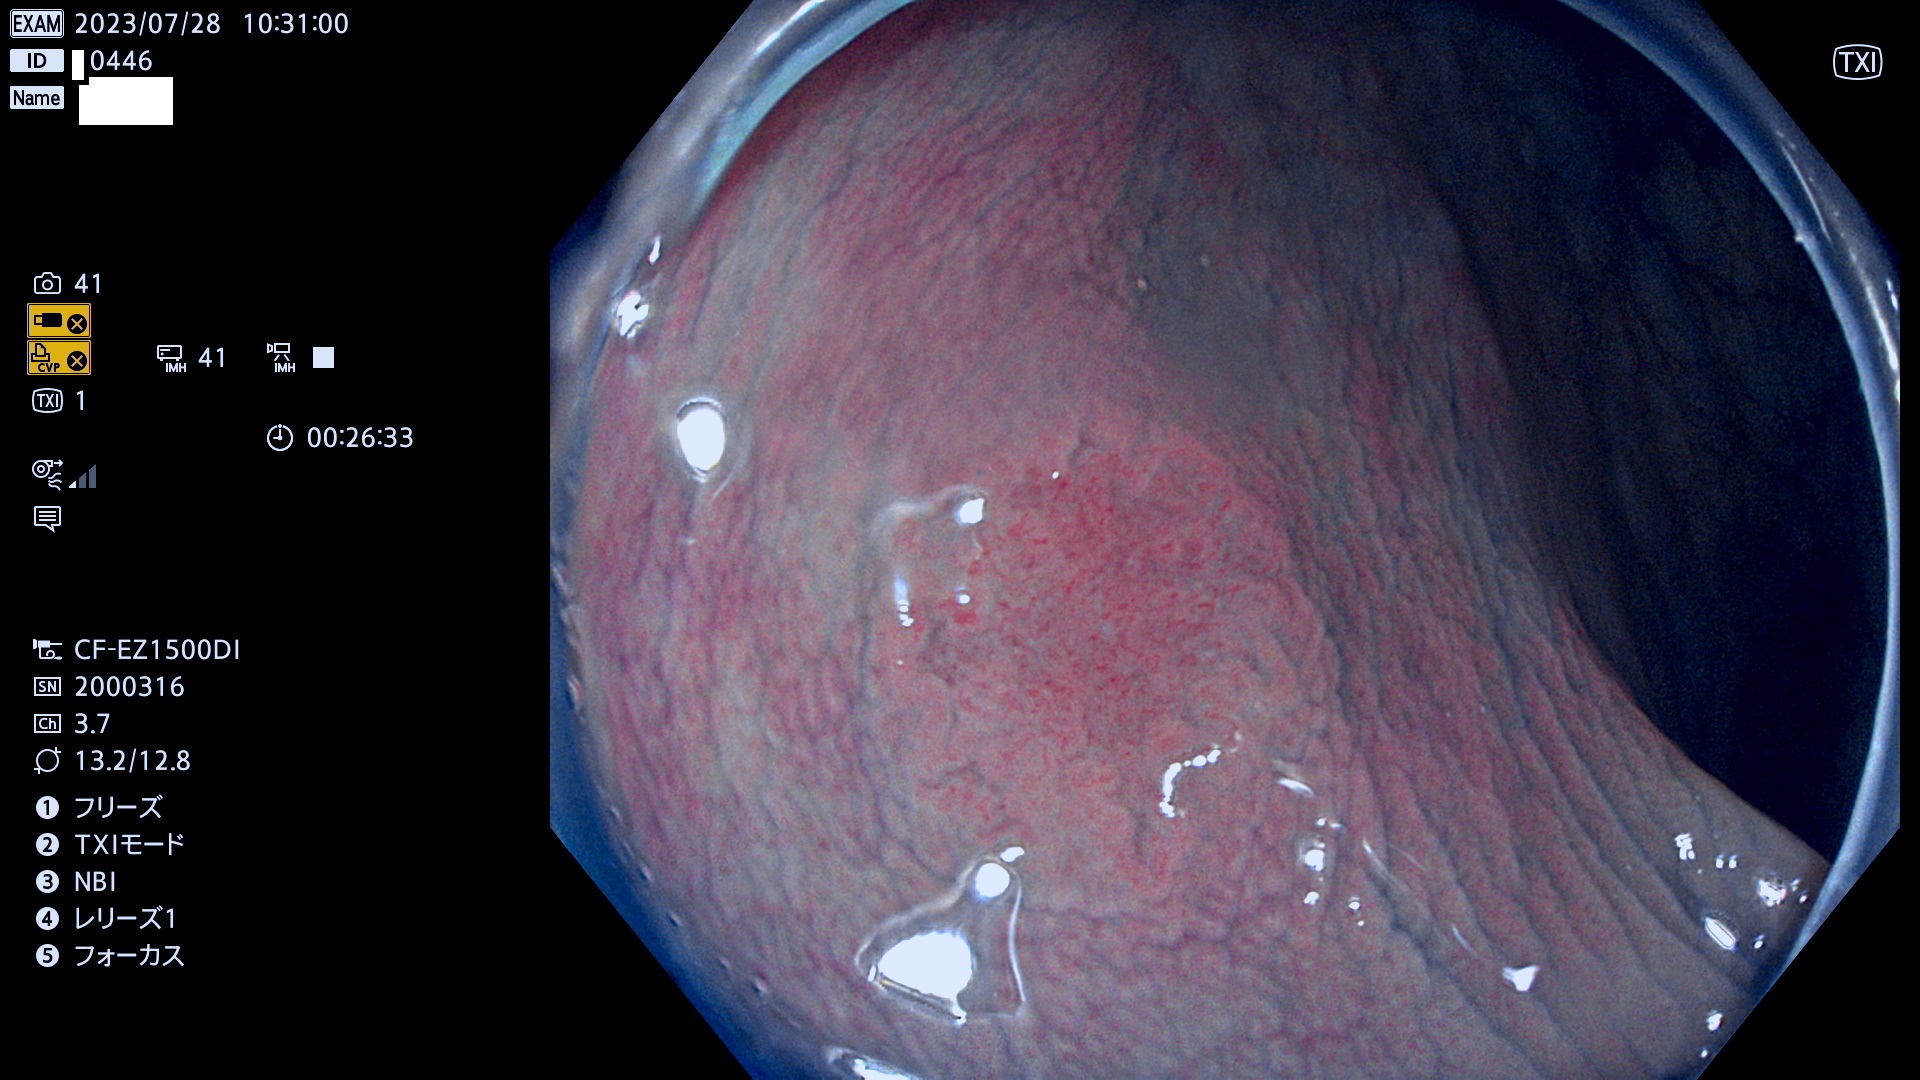

表面型腺腫(Flat Adenoma)の中で、完全に平坦な物をUb、陥凹している物をUcと呼びます。平坦隆起型(Ua)よりも、発見が難しく危険な病変です。このタイプは「内視鏡後・大腸癌の重要犯人」であり、この発見率は「腺腫発見率」よりも、重要な意味があります。

専門的)何故、陥凹していると危険? 癌遺伝子の変異が蓄積すると細胞分裂が盛んになり隆起するのでは?と通常は思われるでしょう。しかし実際は逆です。これは2022年の記事にある「細胞はストレスに直面したら細胞分裂を止める(細胞老化に入り休眠する)という生命の基本的現象」によるものです(Oncogene Stress)。細胞老化を起こすのが癌抑制遺伝子で、この安全装置(ブレーキ)が壊れると癌になります(休眠からの覚醒)。ですから陥凹は「まだ癌では無いが癌化の直前」を意味します。特に「小サイズなのに陥凹している」病変は短期間に腫瘍進化(⇒2021年記事)が起きたことを意味します(=ゲノム不安定性

専門的)Uc=De Novo癌? 内視鏡の解像度が低かった時代、このような説もありました。しかし今日の高精度内視鏡では良性の微小なUc型腺腫が日常的に見つかります。私見ですが「Ucこそが多段階発癌(Adenoma-Carcinoma Sequence)のMain Route」と考えます。

毎週の検査(木・金・土・日)に発見されたUb、Uc型・腺腫を、その週の日曜の夜にUPし1週間、提示します。

抽出の対象期間 2023年7月27日(木)〜7月30(日)の4日間(48件の検査)11件